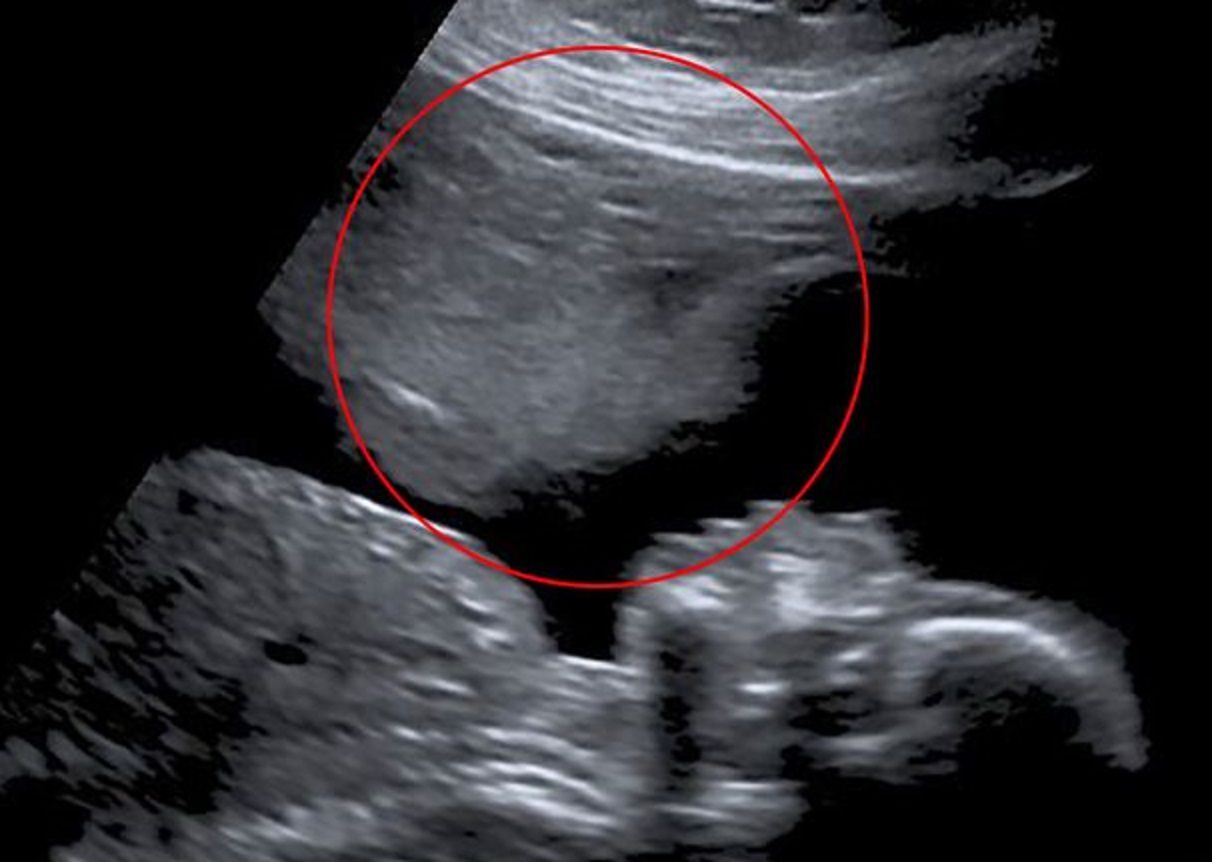

Płód jest chroniony przez płyn owodniowy i worek owodniowy, a także przez zaciśniętą szyjkę macicy. Dlatego nie ma możliwości, aby partner mógł w jakikolwiek sposób dotknąć głowy waszego dziecka. Nawet w trzecim trymestrze ciąży, kiedy dziecko rośnie bardzo szybko i zbliża się do pochwy, głęboka penetracja nie stanowi dla niego zagrożenia.